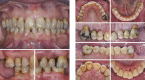

Figures